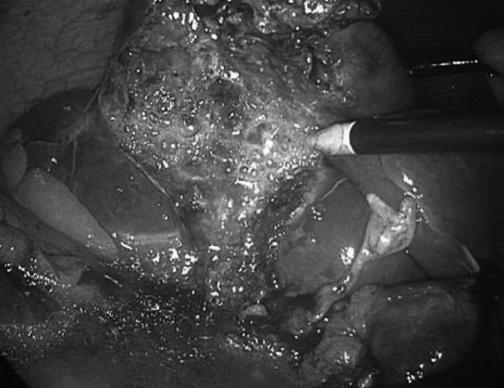

Emergency laparoscopic cholecystectomy was successfully performed during which bubbling of the gallbladder wall was observed. Intraoperative cholangiography revealed no bile duct stones or biliary obstruction. The patient made an unremarkable recovery from surgery with no postoperative complications or admission to the intensive care unit. Pathological analysis revealed full-thickness infarctive necrosis of the gallbladder. Bacterial cultures grew Clostridium perfringens.

成功实施了急诊腹腔镜胆囊切除术,术中观察到胆囊壁有气泡。术中胆管造影显示无胆管结石或胆道梗阻。患者术后恢复顺利,无术后并发症,也未入住重症监护病房。病理分析显示胆囊全层梗死性坏死。细菌培养培养出产气荚膜梭菌。